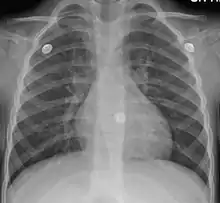

Вирусная инфекция является причиной более чем 90% случаев заболевания[8]. Бактерии встречаются лишь в 1 %—10 % случаев[9], однако их роль в развитии острого бронхита является спорной, поскольку бактериальная инвазия пока не обнаруживалась при анализе проб бронхиальной ткани[10]. Вирусы могут распространяться по воздуху при кашле или при прямом контакте[8]. Факторы риска включают воздействие табачного дыма, пыли и загрязнения воздуха. Небольшое количество случаев связано с высоким уровнем загрязнения воздуха или с бактериями, такими как Mycoplasma pneumoniae или Bordetella pertussis[11]. Диагноз обычно основывается на симптомах[12]. Цвет мокроты не указывает на вирусную или бактериальную инфекцию[13]. Определение патогена среди амбулаторных пациентов обычно не требуется[14]. Схожие с острым бронхитом симптомы могут быть и при других заболеваниях, которые включают в себя астму, пневмонию, бронхиолит, бронхоэктазы и ХОБЛ[15][16]. Рентген грудной клетки может быть полезен для выявления пневмонии.

Не существует каких-либо надёжных специфических тестов или диагностических признаков, с помощью которых можно установить диагноз острого бронхита[50][51]. Биомаркеры могут помочь в определении пациентов, для которых пользу могут принести антибиотики[14]. При подозрении на пневмонию может быть произведён тест на C-реактивный белок, а при сомнении в его результатах диагноз может быть подтверждён или отклонён с помощью рентгенографии грудной клетки[52]. Рентген грудной клетки полезен для исключения пневмонии у людей с лихорадкой, учащенным пульсом, учащенным дыханием или у пожилых людей, поскольку в этих случаях пневмония встречается чаще[16].